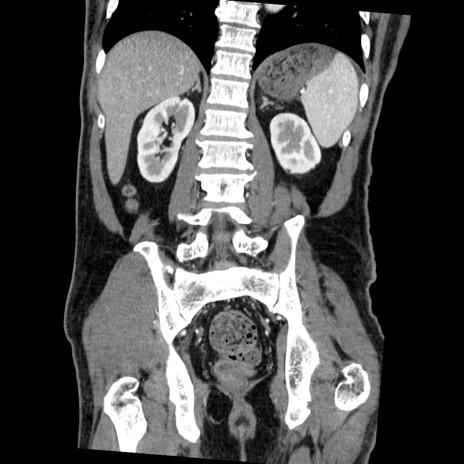

症例22(冠状断像)

【症例】50歳代男性

【主訴】腹痛

【現病歴】AVMからの被殻出血のため回復期リハ病棟入院中。 本日午後3時頃急に下腹部痛が出現した。

【既往歴】AVM、被殻出血、虫垂炎、高血圧

【身体所見】意識晴明、左半身不全麻痺、会話の理解は良好、36.5°C、腹部:膨隆、全体に板状硬、下腹部正中に圧痛点あり、反跳痛-、筋性防御不明、右下腹部にope scar

【データ】WBC 9400、CRP 0.06